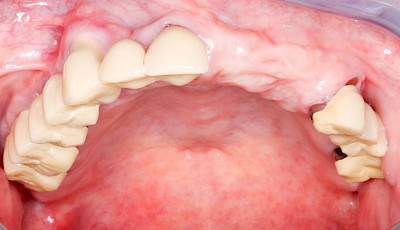

Überbeine im Bereich der Kiefer sind gar nicht so selten. Häufiger im Bereich der Seitenzähne unterhalb des Zahnfleisches, aber auch in der Mitte vom Gaumen. Überbeine haben in dem Sinne keinen Krankheitswert, müssen also nicht operativ entfernt werden, wenn diese nicht stören. Überbeine können ein Anzeichen für Knirschen und Pressen sein.

Gehen die Zähne verloren, baut häufig auch der Kieferknochen ab (Knochenschwund). Die Geschwindigkeit und das Ausmaß des Knochenschwundes ist von vielen Faktoren abhängig. Neben der genetischen Veranlagung spielen auch Überbelastungen in Folge, z. B. bei ständigem Knirschen oder Pressen, eine Rolle. Auch wenn Zahnprothesen Tag und Nacht getragen werden, kann die ständige Belastung der Schleimhäute und des Knochens den Knochenschwund beschleunigen.